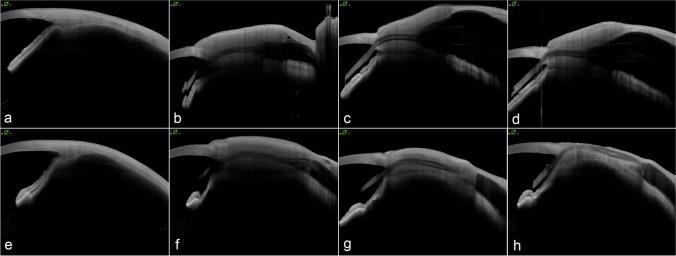

To evaluate a useful, non-contact method for the follow-up of pericardium patch graft changes in patients undergoing PAUL Glaucoma Implant (PGI) surgery using high-resolution anterior segment optical coherence tomography (OCT) to predict tube erosions.

Prospective analysis over six months of tube pericardium patch graft thickness of PGI surgical cases at the University Eye Hospital Bonn, Germany, from November 2021 to August 2022. In all eyes, Tutopatch (RTI Surgical, United States) pericardium was used to cover the implant intra-operatively. Anterior segment OCT (AS-OCT, Heidelberg ANTERION Swept-Source-OCT) examinations were performed following a standardized protocol to measure quantitative and qualitative aspects of the patch grafts before surgery, and at three and six months after surgery.

Twenty-six eyes of 26 patients were included. Thickness of the patch material was 1188 µm (IQR 415 µm) directly after implantation and decreased over time to 1068 µm (IQR 478 µm) at 3 months and 846 µm (IQR 677 µm) at 6 months. No significant differences between groups were shown concerning gender (p = 0.128), ethnicity (p = 1.000), age (p = 0.741), glaucoma type (p = 0.173), other concurrent diseases (p = 0.302), former glaucoma surgeries (p = 1.000) and the quadrant of implantation (p = 0.555). Five eyes developed implant exposure. When comparing eyes with and without tube exposure, no significant differences were shown in average patch thickness above the tube directly after implantation (p = 0.476). However, significant differences in average thickness were observed at 3 months (p = 0.013) and 6 months (p = 0.005).

Pericardial patch grafts tend to thin over time which can be assessed by AS-OCT, the latter proving to be a useful method to follow-up patients who undergo patch graft implantation during PGI surgery. This investigation could potentially help identify patients at risk of tube exposure which in turn could lead to modification of patient management. It could also possibly be used in future studies to find more suitable patch materials.